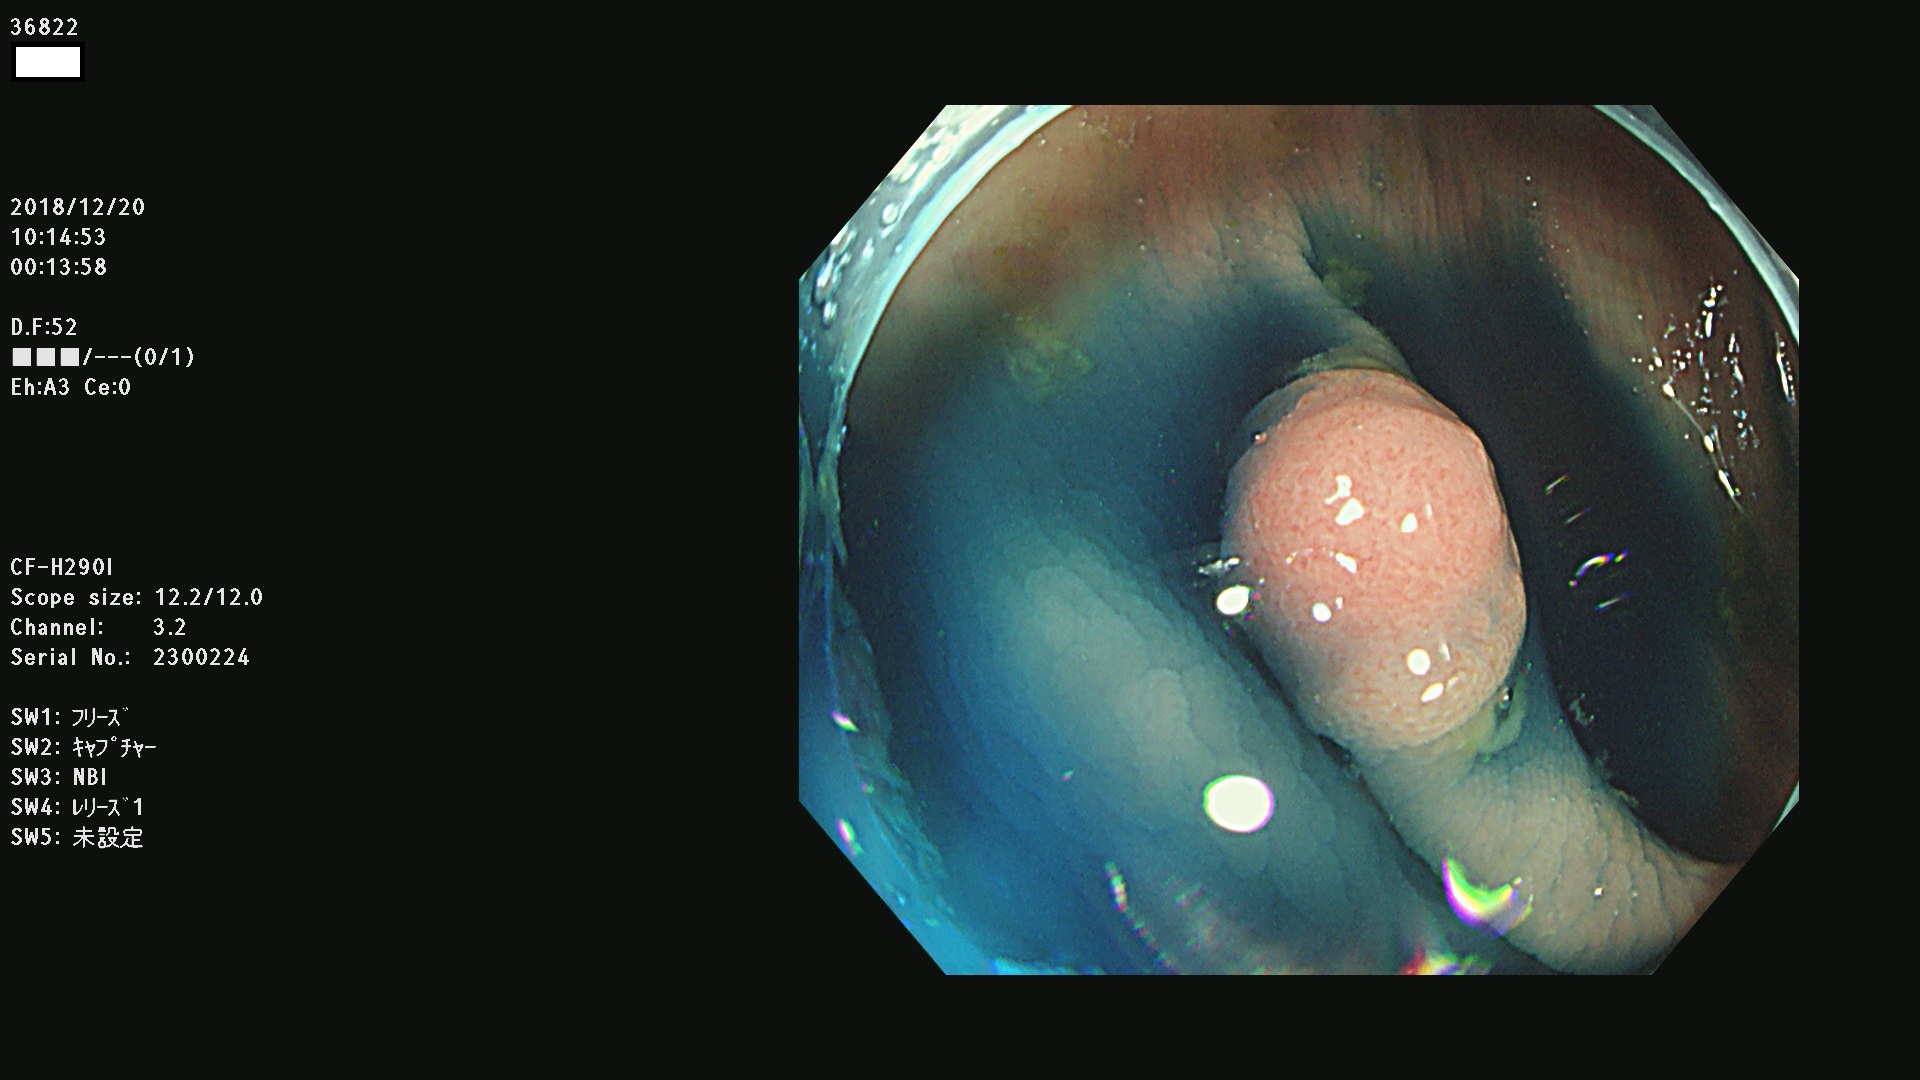

36804 36806 36807 36808 36809 36810 36811 36813 36815 36816 36817 36818 36820 36821 36822 36824 36825 36826 36828 36829 36830 36831 36832 36833 36834 36835 36837 36840 36841 36842 36845 36846 36848 36849 36851 36852 36853 36854 36855 36857 36859 36860 36861 36862(SSAPのみ) 36863 36864 36866 36868 36869 36870 36873 36875 36877 36878 36879 36881 36882 36883 36884 36885 36886 36887 36888 36889 36891 36892 36893 36894 36895 36896 36897 36898 36899

発見困難で危険性の高い平坦型病変(上記100名より抽出)